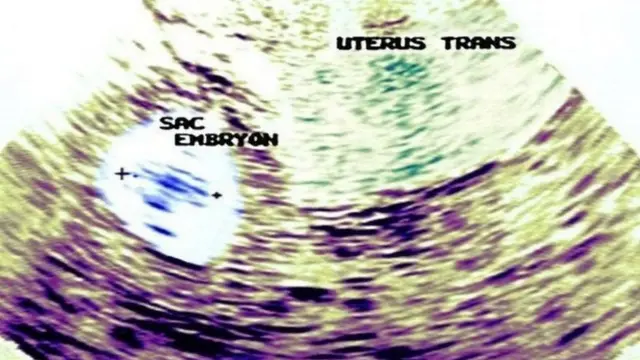

फोटो स्रोत, DR.SAILAJACHANDU

गर्भधारणेच्या पहिल्या तीन महिन्यात स्कॅनिंग करतात. यात गर्भाची वाढ व्यवस्थित होत आहे का? मोलार प्रेगनन्सीची लक्षणं आहेत का? या सगळ्या गोष्टी तपासल्या जातात. मात्र, बायोप्सी केल्यानंतरच या आजाराची खातरजमा करता येते.